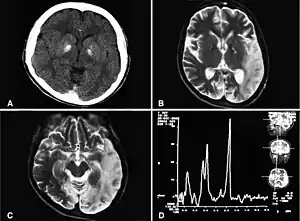

| MELAS症候群病人的腦部電腦斷層影像,可見 基底核 鈣化、小腦萎縮,病人還有乳酸升高的現象。 | |

MRI:於腦皮質可見不同缺血變化階段的多處類似梗塞的区域,這些區域的分布不符合任何已知血管分布区域。最初的病变通常发生在枕叶或顶叶,最终犯及小脑、大脑皮层、基底神经节和丘脑。

血清和脑脊液中的乳酸水平常會升高。 MR 頻谱在受影响與未受影响的大脑区域都可能顯示乳酸的峰值升高。肌肉切片可見不整齐的红色纤维。不過應該要先进行基因评估,如此對於大多數的病人就不需要進行肌肉切片。诊断可以基於分子生物學檢查或依照臨床判斷: